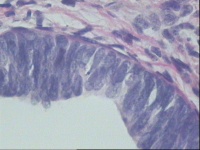

子宫内膜不典型增生?

性别

女

年龄

53岁

异常子宫出血

子宫内膜

灰白色碎组织一堆,大小约2.1*1.5*1CM。

无非典型性子宫内膜增生。